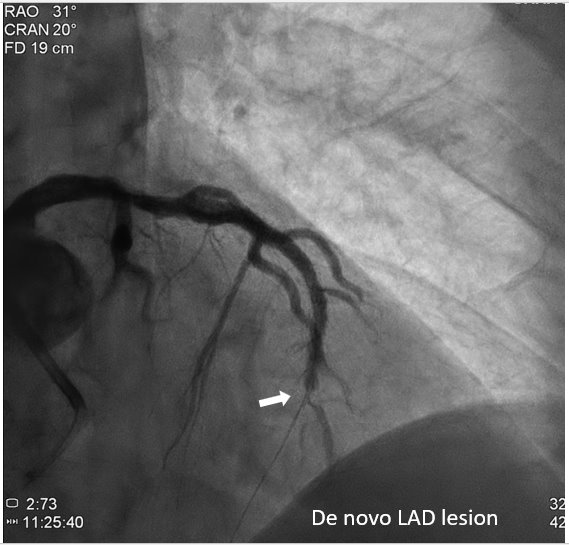

The patient received primary percutaneous coronary intervention (PCI) with balloon angioplasty (POBA) and a drug-eluted stent (DES) for middle LAD. Three days later he underwent staged PCI for RCA. After wire externalization via rendezvous technique, the patient developed acute angina, diaphoresis, and hypotension. Angiogram found a de-novo LAD lesion just distal to the stent.

During the staged PCI, antegrade approach with escalating guidewires ended up in subintimal space; retrograde approach from the first LAD-septal branch failed because there was difficulty crossing the existing mid-LAD stent. Further attempts from the third septal branch successfully reached the distal cap of the CTO via proximal descending artery, finally entering the antegrade guide extension catheter by rendezvous technique. After wire externalization and POBA for RCA, the patient became agitated from acute angina, diaphoresis and hypotension. Angiogram of LAD found an acute de novo LAD lesion adjacent to the distal stent edge, leaving only TIMI-1 flow. We stopped the RCA procedure and wired LAD, performed POBA at the de novo LAD lesion and restored coronary blood flow. Then we continued PCI of RCA with POBA followed by the deployment of two DES. Final angiogram showed adequate stent expansion and TIMI-3 flow in RCA. The patient was discharged with no further complications. Follow-up echocardiogram three months later showed improved wall motion and ejection fraction, indicating good myocardial recovery.